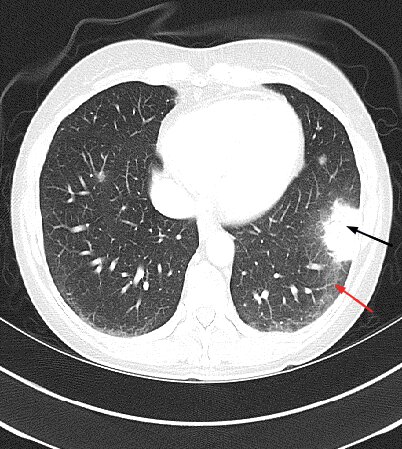

Affects women of childbearing age. Associated with spontaneous pneumothorax and chylous effusions. Chest CT scan shows cystic disease that is diffuse in distribution. Diagnosis?

What is: Lymphangioleiomyomatosis (LAM)